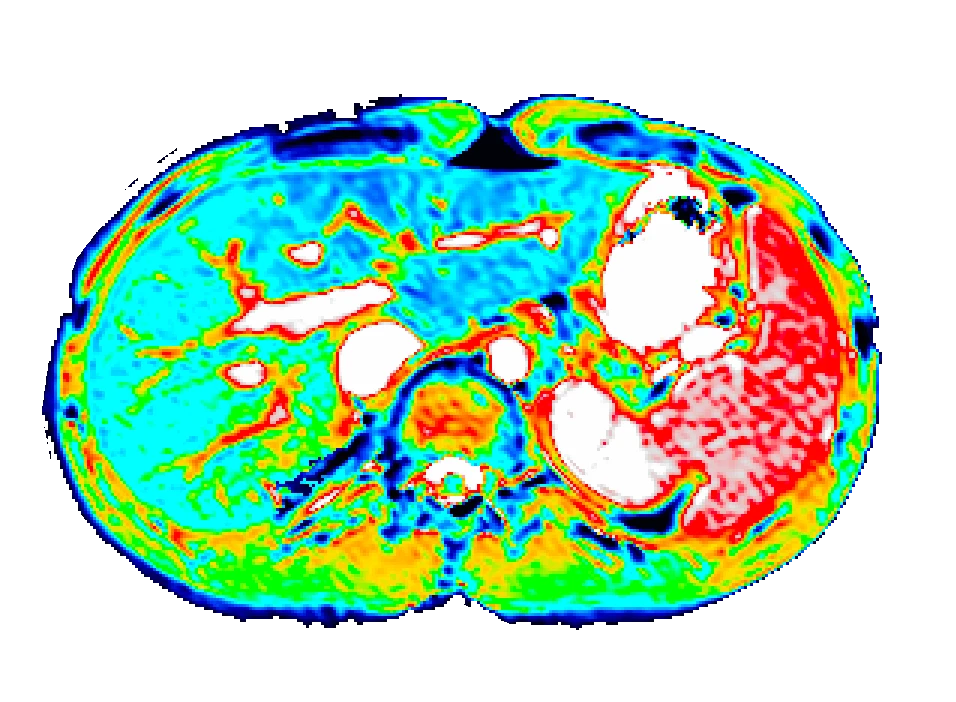

We use dynamic contrast-enhanced MRI (DCE-MRI) of gadoxetate to measure liver transporter function. We use relaxation time measurements to assess tissue status.

Berks M, Little RA, Watson Y, Cheung S, Datta A, O'Connor JPB, Scaramuzza D, Parker GJM, A model selection framework to quantify microvascular liver function in gadoxetate-enhanced MRI: Application to healthy liver, diseased tissue, and hepatocellular carcinoma. Magn Reson Med. 2021 Oct;86(4):1829-1844.